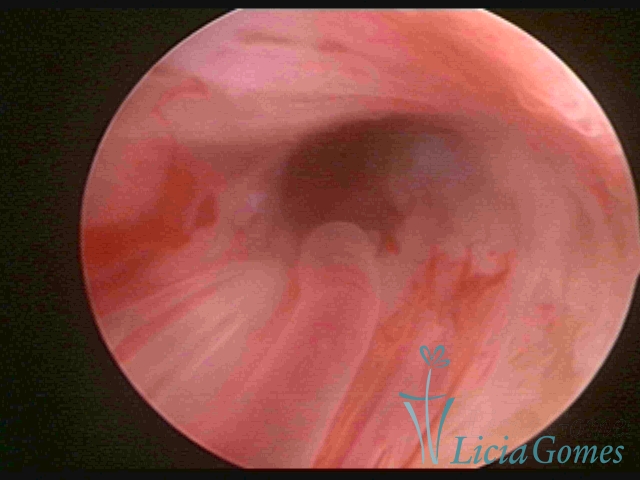

ENDOCERVICAL POLYPS

Benign tumors resulting from the reactive focal proliferation to inflammatory processes or hyperestrogenism situations, which may be sessile (with a large implantation) or stalked.